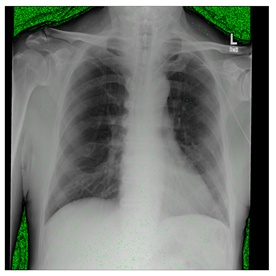

Figure 12.

Sampled images in the tested benchmark databases: (a) Breast-MRI-NACT-Pilot (breast), (b) ACRIN-DSC-MR-Brain (brain), (c) NIH (chest), (d) Lung-PET-CT-Dx (lung), (e) Prostate-MRI (prostate), and (f) Other grayscale standard images.

ANIH is an X-ray type image database collecting chest medical images. Some samples are shown in Figure 12c.